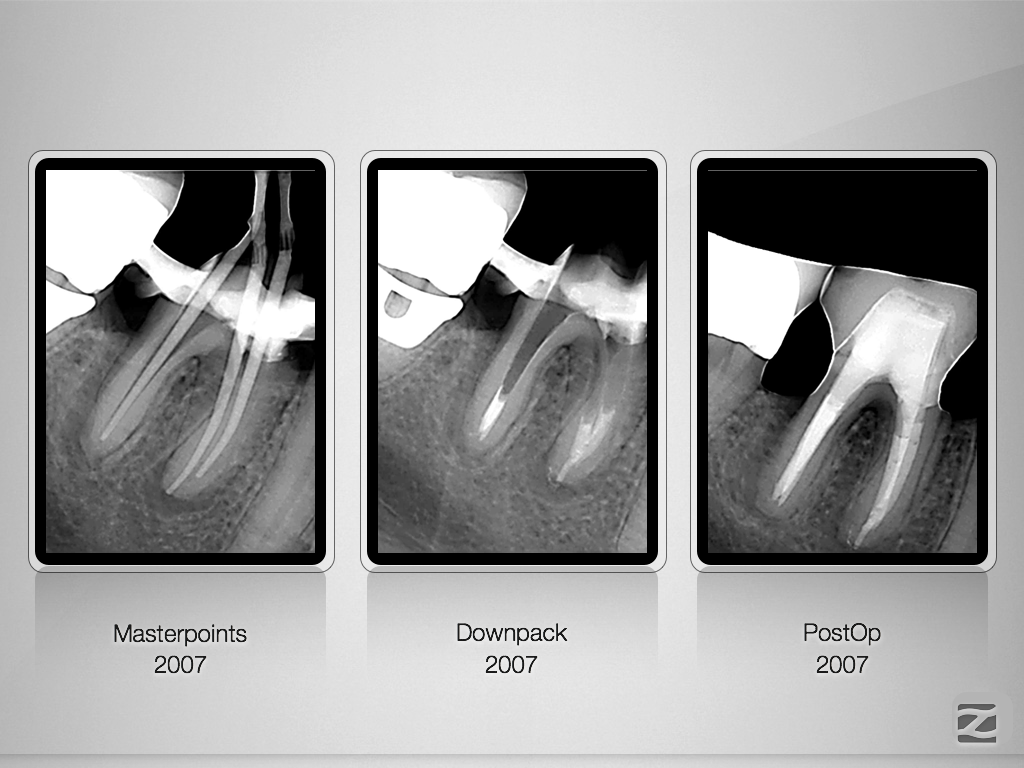

46D.002

8-Jahres-Recall